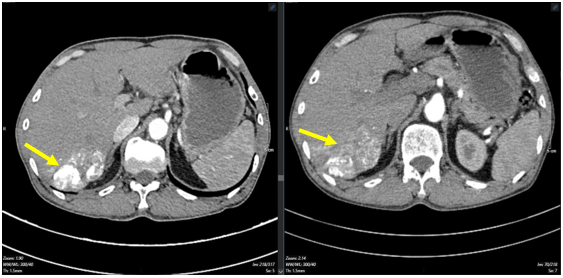

-  Chụp cắt lớp vi tính bụng: (Tháng 12/2020) Hình ảnh khối ngấm thuốc gan phải: Nhu mô phân thùy VII có khối kích thước 37x35mm, ngấm thuốc thì động mạch, ngấm thêm vào trung tâm thì tĩnh mạch cửa, vùng trung tâm không thấy ngấm thuốc. Gan:Kích thước bình thường, bờ đều. Sỏi túi mật. Sỏi thận phải. Nang nhỏ thận trái.

Hình 1: Nhu mô phân thùy VII có khối kích thước 37x35mm, ngấm thuốc thì động mạch, ngấm thêm vào trung tâm thì tĩnh mạch cửa,vùng trung tâm không thấy ngấm thuốc. (mũi tên vàng)